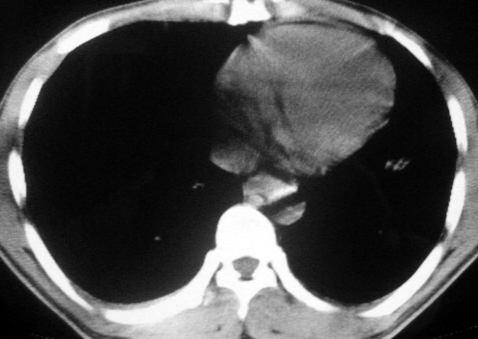

男,36岁,一月前醉酒淋雨后发热咳嗽,气短进行性加重.

抗生素治疗无效,痰检(一).

影像诊断:结核? 还有其他考虑吗?

双肺内中部见略不对称性蝶翼状高密度区,边界不清,部分呈磨玻璃样密度,并可见含气支气管征。肺门、纵隔内未见肿大淋巴结影。无胸腔积液。

考虑:1、肺炎,建议进一步查冷凝集试验除外支原体肺炎;

2、不除外霉菌感染。

双肺斑片状密度均匀病灶,边界模糊可见充气支气管征,上野多于下野,不支持结核,1肺内感染,2查肾功,中心型肺水肿待除外.

双肺中上野对称分布蝶翼样不均匀密度增高影,有支气管充气征,纵隔未见肿大淋巴结,发病突然,抗炎治疗无效,还是要考虑结核。

还是考虑肺水肿!蝶翼征.肺门增大,肺血管影增粗,!!病变累及中内带为主!要排外支原体感染.

支持: 双肺内中部见略不对称性蝶翼状高密度区,边界不清,部分呈磨玻璃样密度,并可见含气支气管征。肺门、纵隔内未见肿大淋巴结影。无胸腔积液。